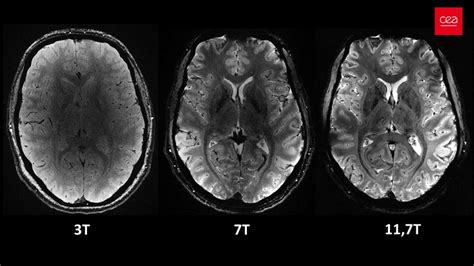

Diagnostika vrodených chýb maternice sa zakladá predovšetkým na klinických ťažkostiach pacientky a následnom gynekologickom vyšetrení. Na získanie detailnejších informácií sa následne využívajú zobrazovacie metódy, ako je ultrazvuk a magnetická rezonancia. V minulosti bola bežne používaná hysterosalpingografia, avšak táto metóda mala svoje obmedzenia, vrátane radiačnej záťaže a nižšej presnosti. Dnes sa hysterosalpingografia využíva len zriedkavo, najmä na potvrdenie priechodnosti vajíčkovodov.

Vyšetrenie na diagnostiku MDA nevyžaduje špeciálnu prípravu, s výnimkou mierneho naplnenia močového mechúra, čo zlepšuje vizualizáciu panvových orgánov. Ideálnym časom na vykonanie vyšetrenia je druhá polovica menštruačného cyklu. Vo väčšine prípadov nie je potrebné ani podanie kontrastnej látky. Na získanie kvalitných obrazov sa používajú štandardné T1 a predovšetkým T2 vážené sekvencie magnetickej rezonancie, zobrazené v troch na seba kolmých rovinách, ktoré sú upravené podľa dlhej osi tela maternice.